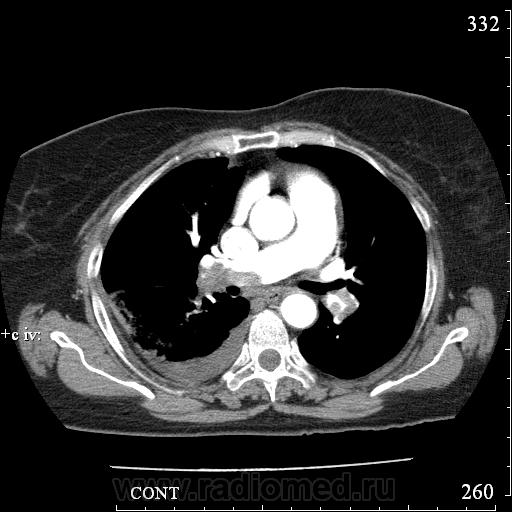

Еще один случай диагностики ТЭЛА методом КТ-ангиографии у женщины 59 лет. Основная клиническая жалоба - выраженная одышка. Определяется: полный дефект наполнения в системе правой ЛА (бифукация и нижнедолевая), неполный дефект наполнения в левой ЛА (нижнедолевая), пристеночные тромбы по задней стенке в области бифуркации обеих легочных артерий. Инфаркт (массивное кровоизлияние) нижней доли правого легкого. Правосторонний малый (120см3) гидроторакс. Несмотря на выраженные тромбы, поперечники легочных артерий - в пределах нормы.; на нативной (безконтрастной) КТ - тромбы не видны. Несмотря на почти полный дефект наполнения в левой нижнедолевой артерии, изменений в легочной ткани левого легкого нет. Также приводится топограмма, как вариант, приближенный к рутинной рентгенограмме